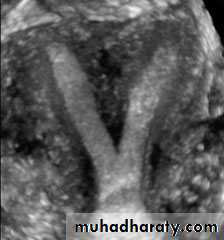

• Intramural leiomyomata are frequently visualized. Examples of fibroids which compromise the contours of the endometrial cavity are shown (A–D). Refraction artifacts resulting from tissue density interfaces and the texture of the fibroids often aid in their identification.Congenital anomalies of uterus

Unicornuate uterusCongenital anomalies of uterus

Bicornuate Bicollis Uterus• Congenital anomalies of uterus

• Didelphic uterus with Left sided hematometra• Congenital anomalies of uterus

• Subseptate Uterus

• Congenital anomalies of uterus

• Complete Septate• Congenital anomalies of uterus

• Arcuate uterusEndometrium